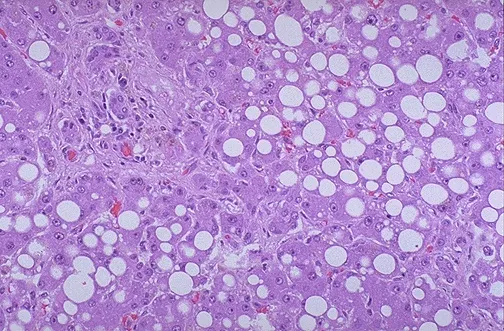

- Steatosis: Abnormal accumulation of triglycerides within parenchymal cells, most commonly the liver. Also seen in heart, muscle, and kidney.

- Microscopy: Clear, sharply demarcated cytoplasmic vacuoles that displace the nucleus. Requires frozen sections with Oil Red O or Sudan Black B for positive staining.